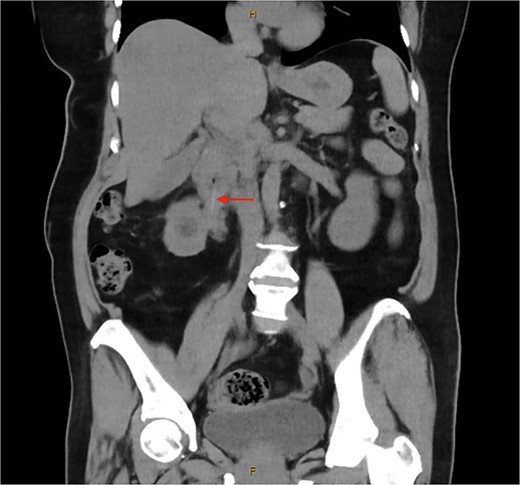

Following ureteric stent removal, she was investigated with a routine interval computed tomography (CT) of the abdomen and pelvis (Fig. 1). This identified a 5 cm radiopaque foreign body in the proximal duodenum. The foreign body was noted to extend extra-luminally into the right renal hilum. There was right hydronephrosis proximal to foreign body, with fat stranding surrounding the right ureter. On retrospective review, this was visualized on previous CT examination. Initial attempt at endoscopic retrieval of the foreign body, which was thought to be a fish bone, was unsuccessful due to distortion of the duodenum from inflammatory changes preventing visualization. Proton-pump inhibition was commenced to reduce inflammatory changes before further attempts at retrieval.

Unenhanced computed tomography of the abdomen and pelvis demonstrating a 5 cm linear radiopaque foreign body extending from the junction of the first and second part of the duodenum into the right renal pelvis.